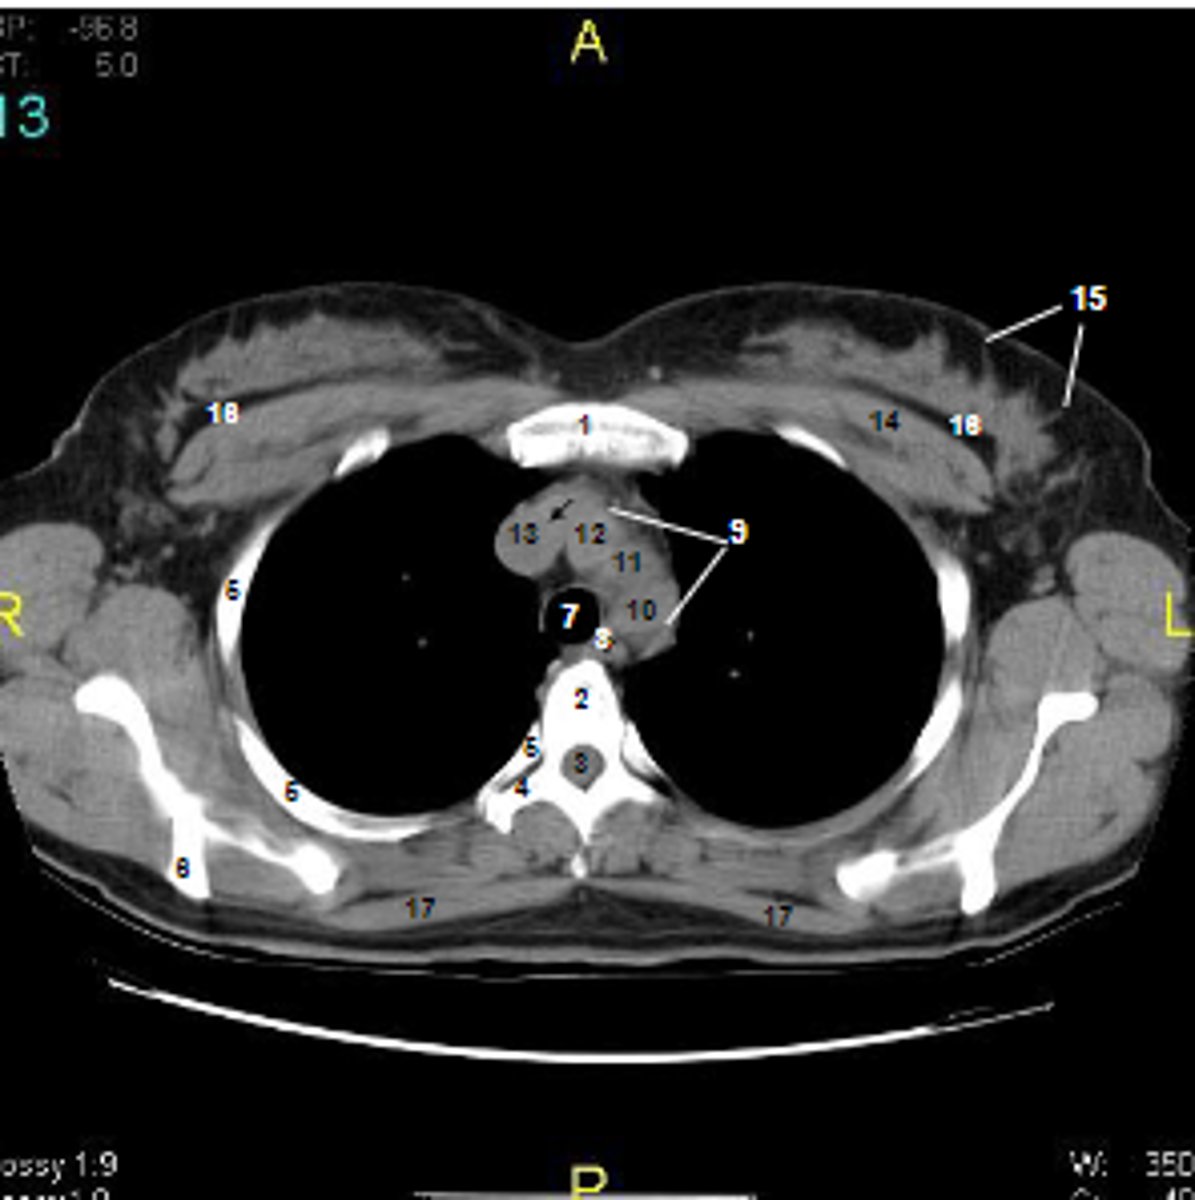

1

at what number is the sternum

2

at what number is the vertebral body

3

at what number is the vertebral canal/ spinal cord

4

at what number is the transverse process of vertebra

5

at what number is the rib

6

at what number is the spine of scapula

7

at what number is the trachea

8

at what number is the esophagus

9

at what number is the arch of aorta

10

at what number is the left subclavian artery

11

at what number is the common carotid artery

12

at what number is the brachiocephalic trunk

13

at what number is the superior vena cava

14

at what number is pectoralis major

15

at what number are Cooper's ligaments

16

at what number is the retromammary space

17

at what number is trapezius